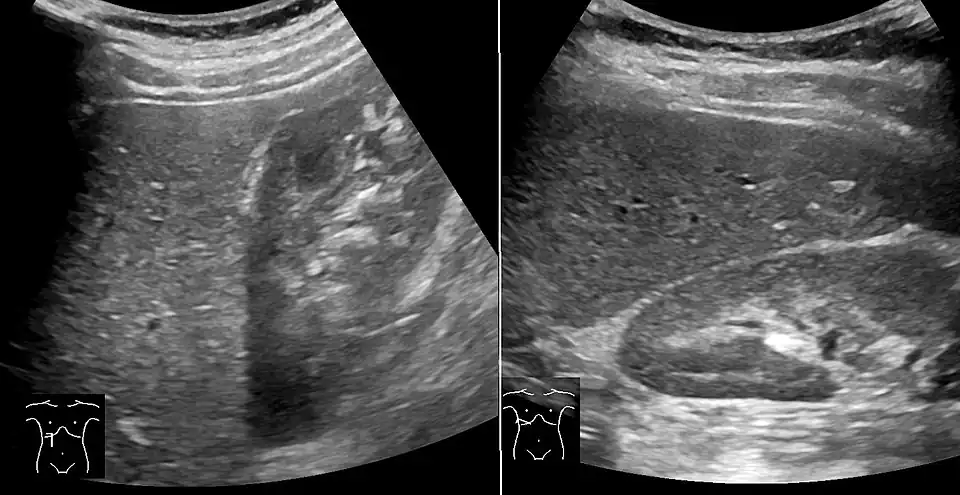

Medical imaging

Liver steatosis (fatty liver disease) as seen on CT

On X-ray computed tomography (CT), the increased fat component will decrease the density of the liver tissue, making the image less bright. Typically the density of the spleen and liver are roughly equivalent. In steatosis, there is a difference between the density and brightness of the two organs, with the liver appearing darker.[12] On ultrasound, fat is more echogenic (capable of reflecting sound waves). The combination of liver steatosis being dark on CT and bright on ultrasound is sometimes known as the flip flop sign.

On abdominal ultrasonography, steatosis is seen as a hyperechoic liver as compared to the normal kidney.